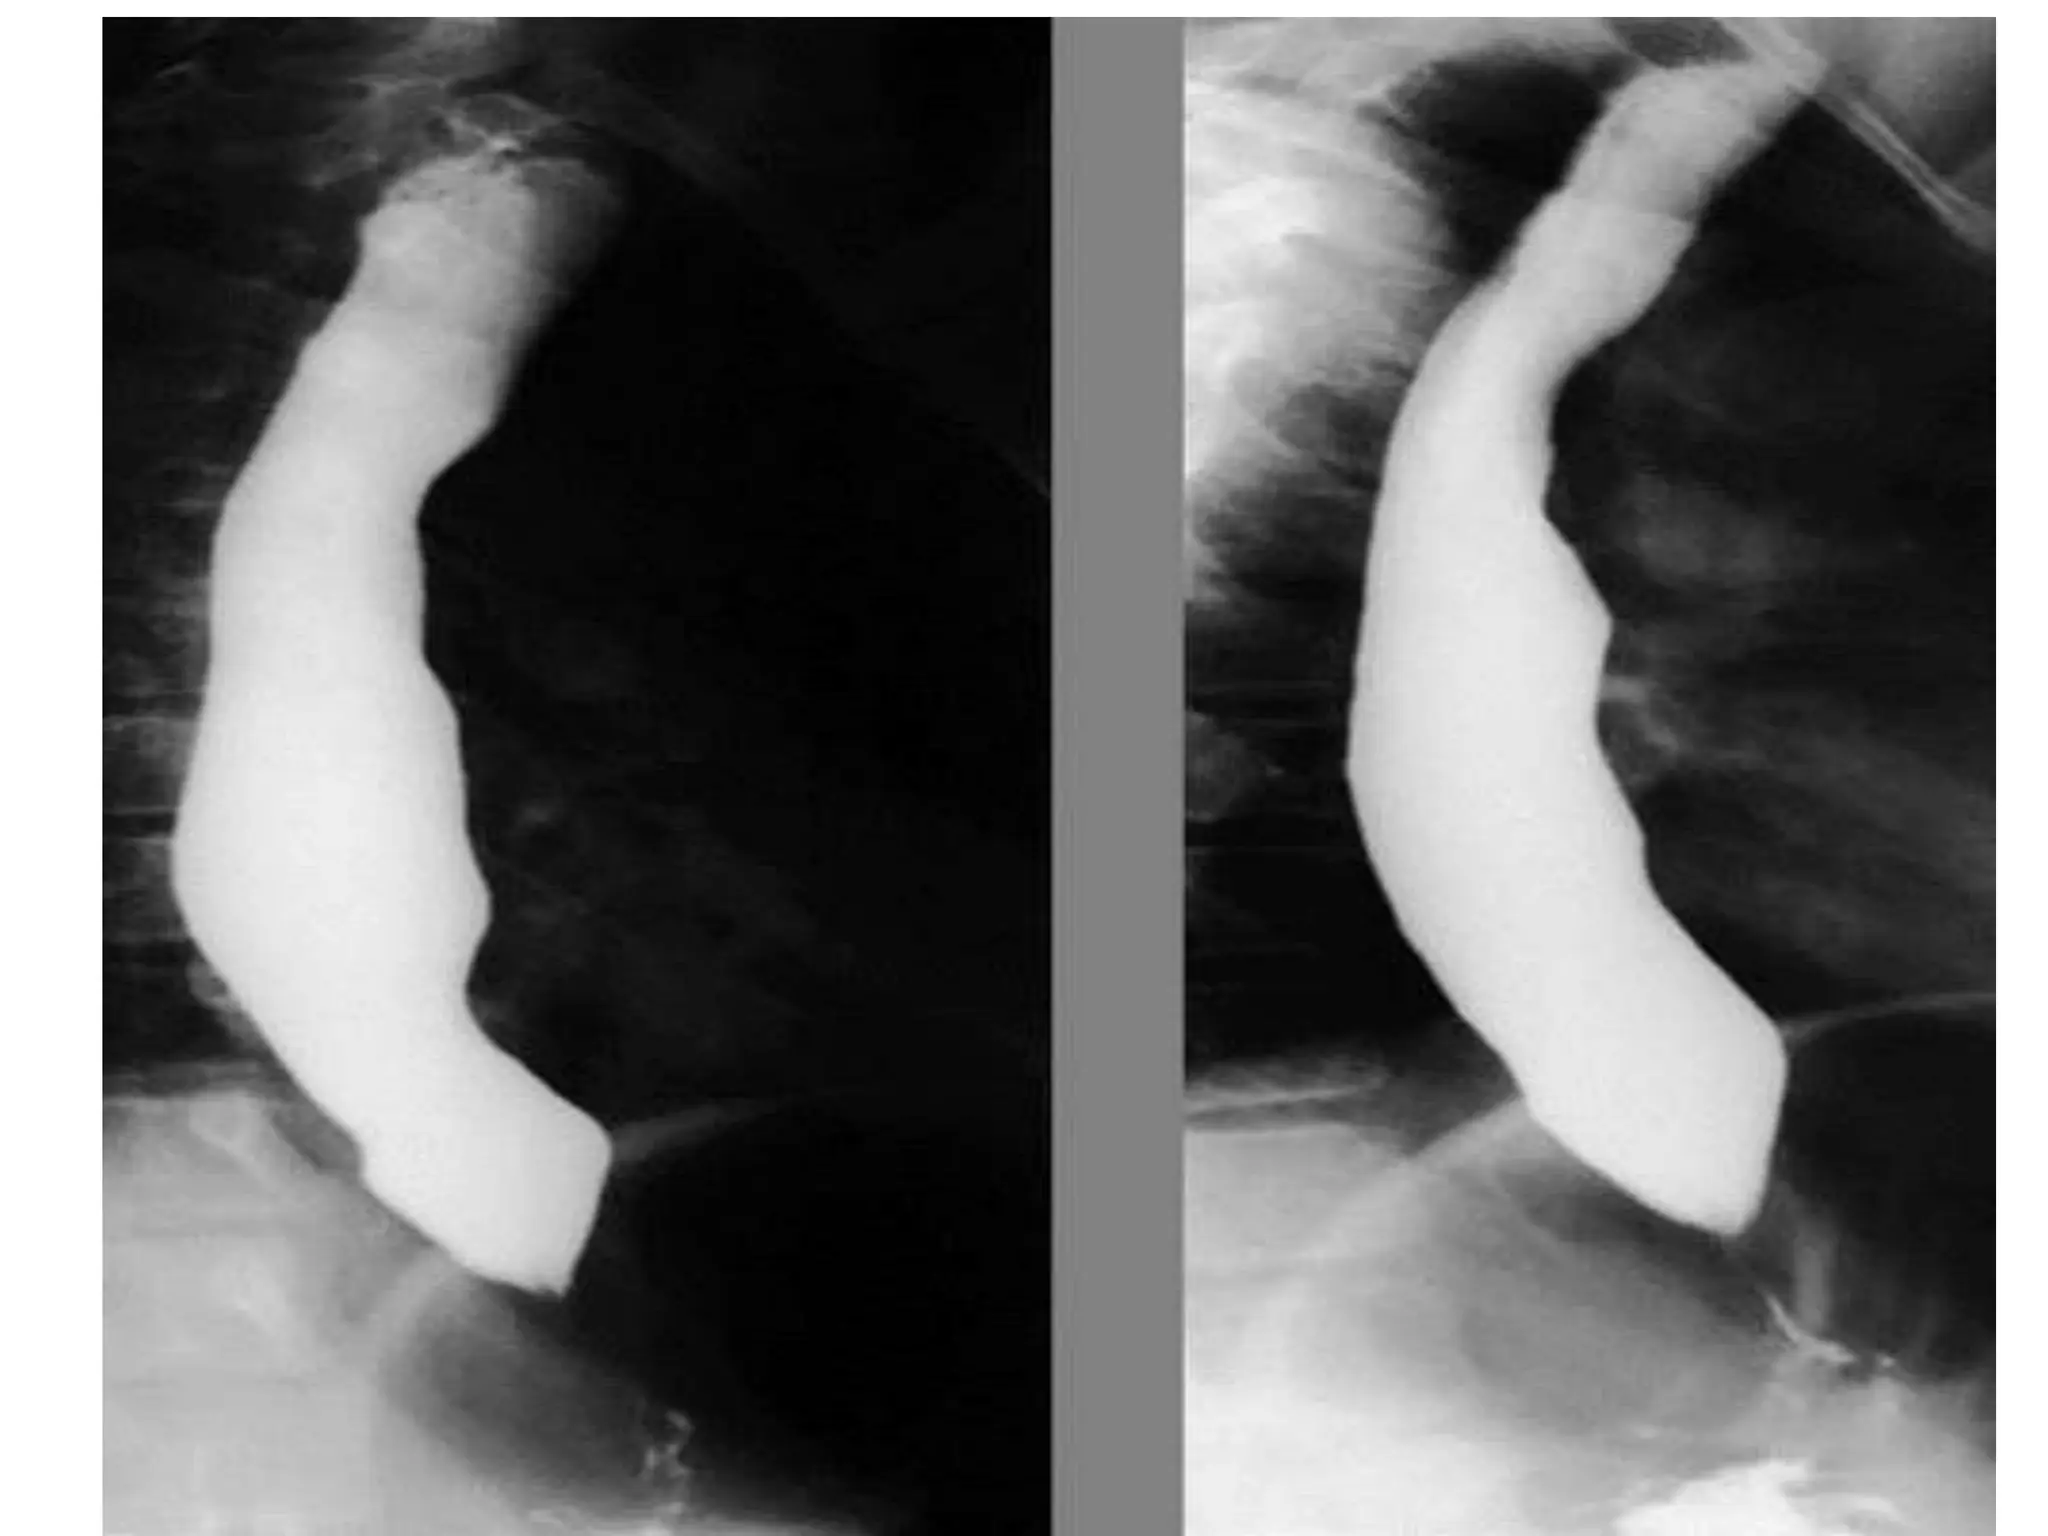

Esophageal stage of swallowing

• Passage of food from

Pharynx to Stomach

Peristalsis

• 2 types of peristalsis

1. Primary peristalsis

2. Secondary peristalsis